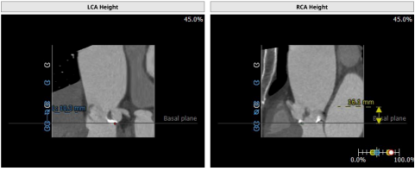

主动脉CT

一方面,左右瓣,瓣叶增厚粘连,导致介入瓣膜植入后,瓣膜挤压下滑风险非常高;

另一方面,无冠窦瓣叶较薄,需预防瓣膜植入后瓣膜向上走的风险;

同时,左右冠脉开口均不高,冠脉开口层面均有瓣叶,窦内空间不大,存在冠脉闭塞风险。

本病例窦部情况可,瓣环周长24mm左右,判断使用VitaFlow24或VitaFlow27号瓣膜。